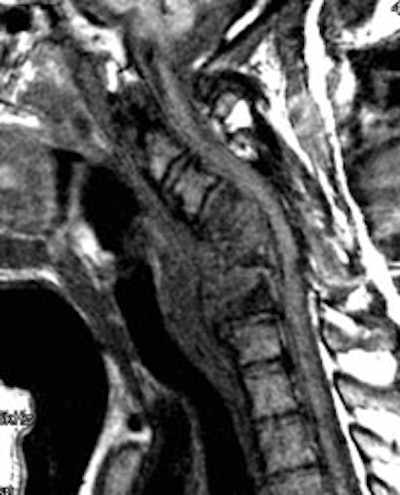

Gallium imaging for vertebral osteomyelitis: The patient below had an extensive cervical spine osteomyelitis involving C4 to C6. A pre-contrast MR image is shown on the left (degraded by motion), and a post-gadolinium image is shown in the center. Gallium-67 imaging revealed increased tracer activity corresponding to the area of abnormality on MR (black arrow) and was going to be used to monitor response to therapy. SPECT imaging would have been beneficial, but the patient could not tolerate the exam. Note the photopenic defect in the area of infection on corresponding Tc99m-sulfur colloid images (top row of nuclear medicine images). |